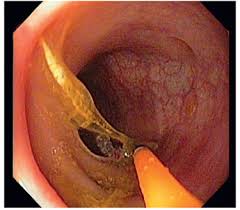

Constituimos una nueva generación de médicos gastroenterólogos en Puebla, altamente capacitados y certificados dentro de la gastroenterología nuestro objetivo es la aplicación de las más altas tecnologías para el diagnóstico y tratamiento eficaz de las enfermedades de esófago, estómago, hígado, vía biliar, páncreas, intestino delgado (duodeno, yeyuno e íleon), intestino grueso (colon) y recto.